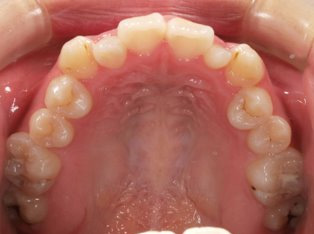

治療前

治療終了前